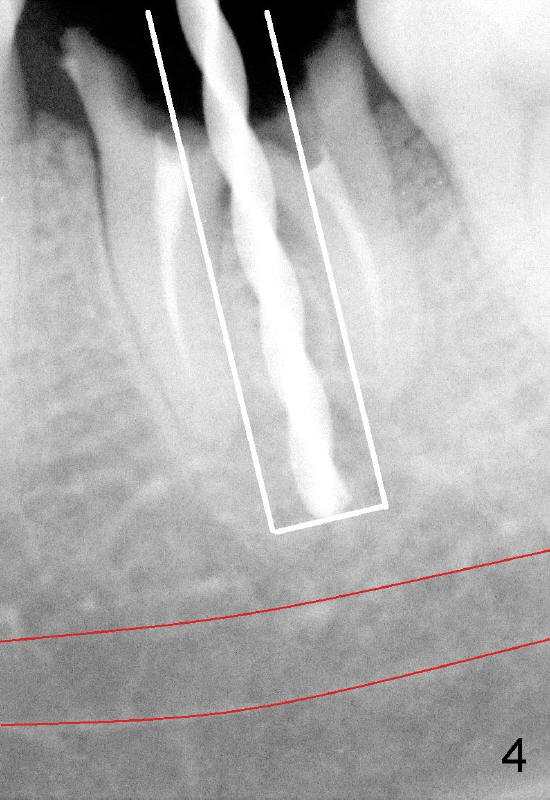

A 41-year-old lady fractures the crown of the lower left 1st molar (Fig.1.2). After removal of the remaining crown (Fig.3*) and exposure of the top of the septum, a pilot drill (D, 1.5 mm) is used to initiate the osteotomy. Drills with increasing diameters could be used to enlarge the osteotomy while the roots are in place (Fig.4: white rectangular outline).